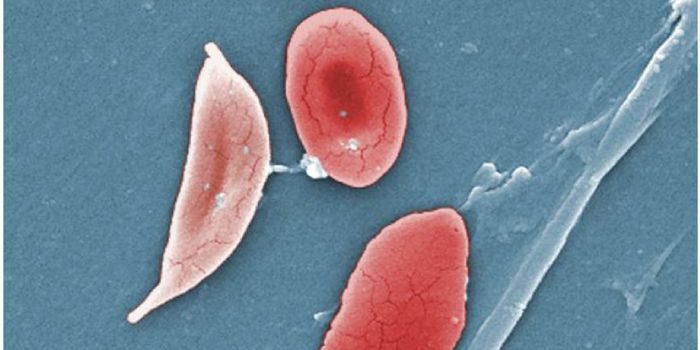

MAY 04, 2025Clinical & Molecular DXBabesiosis is a tick-borne disease that is caused by parasites, which infect red blood cells. The symptoms can present i ...